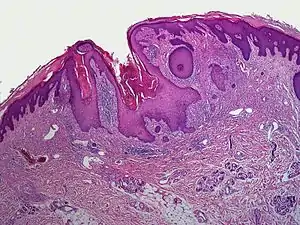

A dilated pore, also known as a dilated pore of Winer, is a cutaneous condition characterized by a solitary, prominent, open comedo on the face or upper trunk of an individual.[1]: 675 Louis H. Winer is credited with discovering the dilated pore. [2][3]

| Dilated pore of Winer |